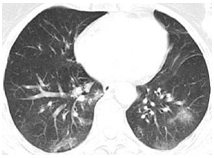

3.胸部影像學(xué)表現(xiàn)

早期呈現(xiàn)多發(fā)小斑片影及間質(zhì)改變,以肺外帶明顯。進(jìn)而發(fā)展為雙肺多發(fā)磨玻璃影、浸潤影,嚴(yán)重者可出現(xiàn)肺實變,胸腔積液少見。

雙肺多發(fā)GGO